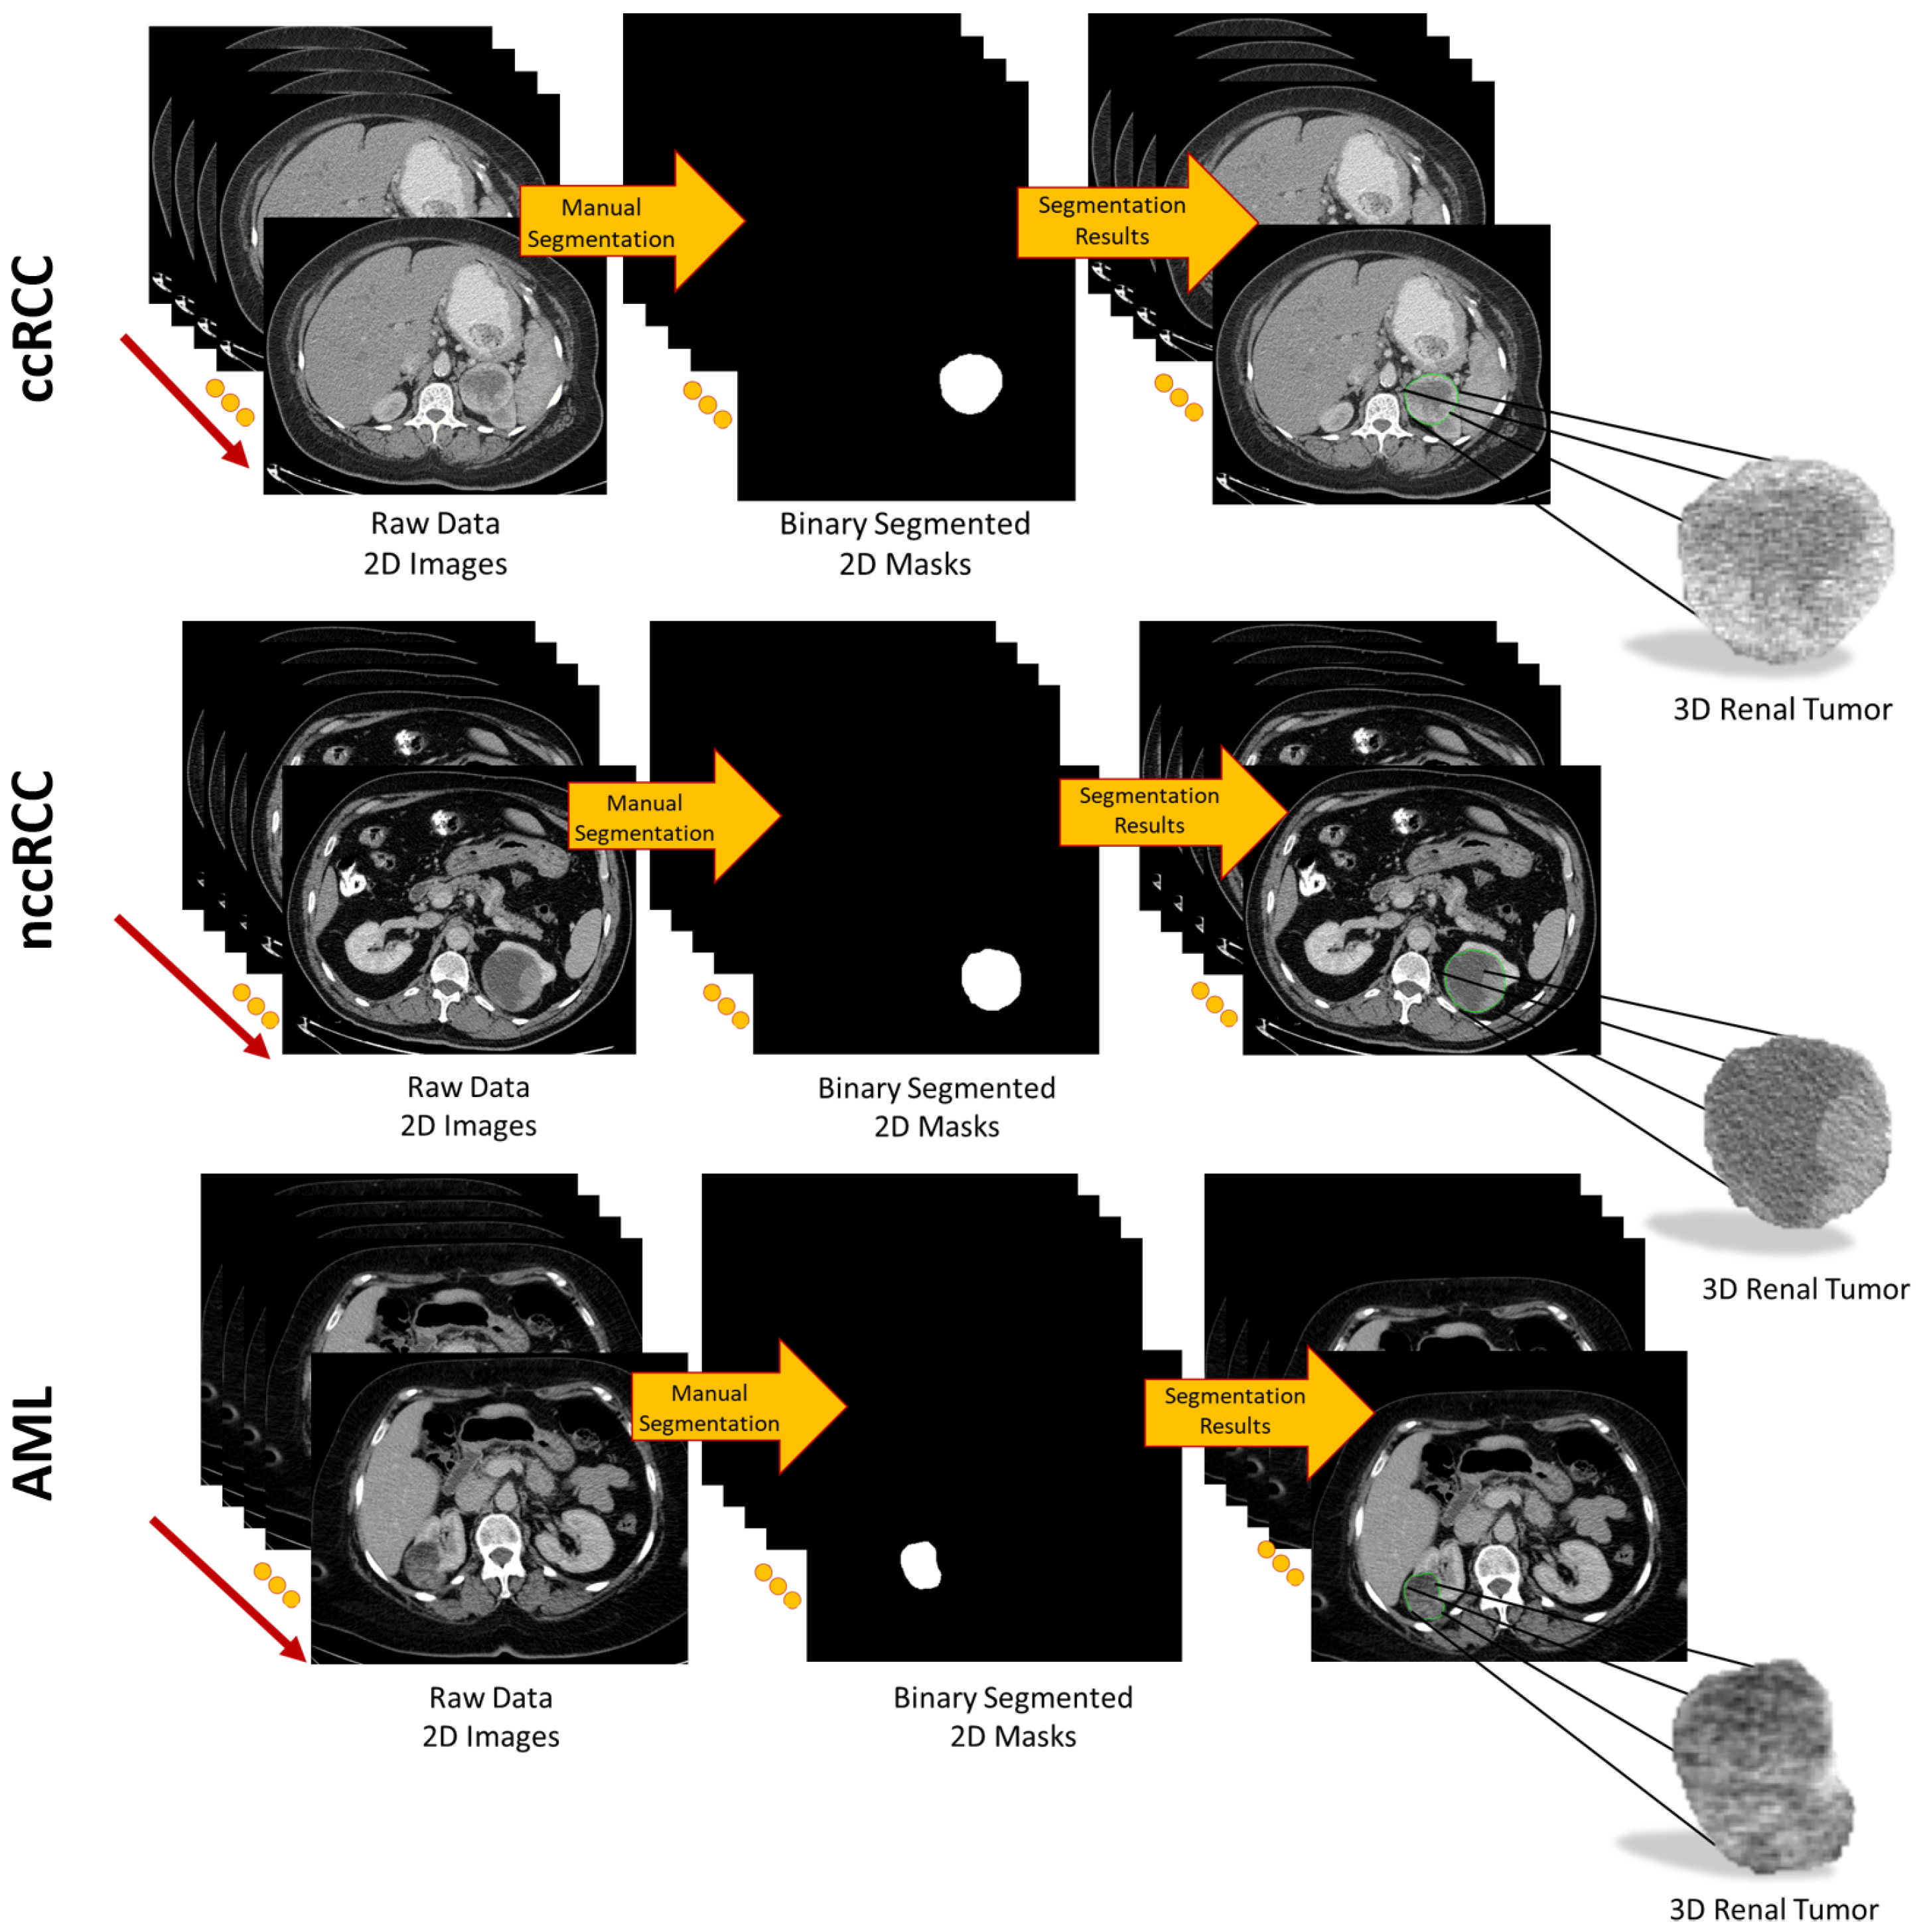

To provide a more accurate extraction of morphological, textural, and functional discriminating imaging features, for each subject, each CT slice intersecting the renal tumor was accurately and manually segmented by expert radiologists to define the 2D ROI. Then, all 2D ROIs were stacked together to construct the 3D renal tumor object (3D ROI), as shown in Figure 2.

Figure 2. Visualization of the segmentation process to obtain 3D renal tumors.